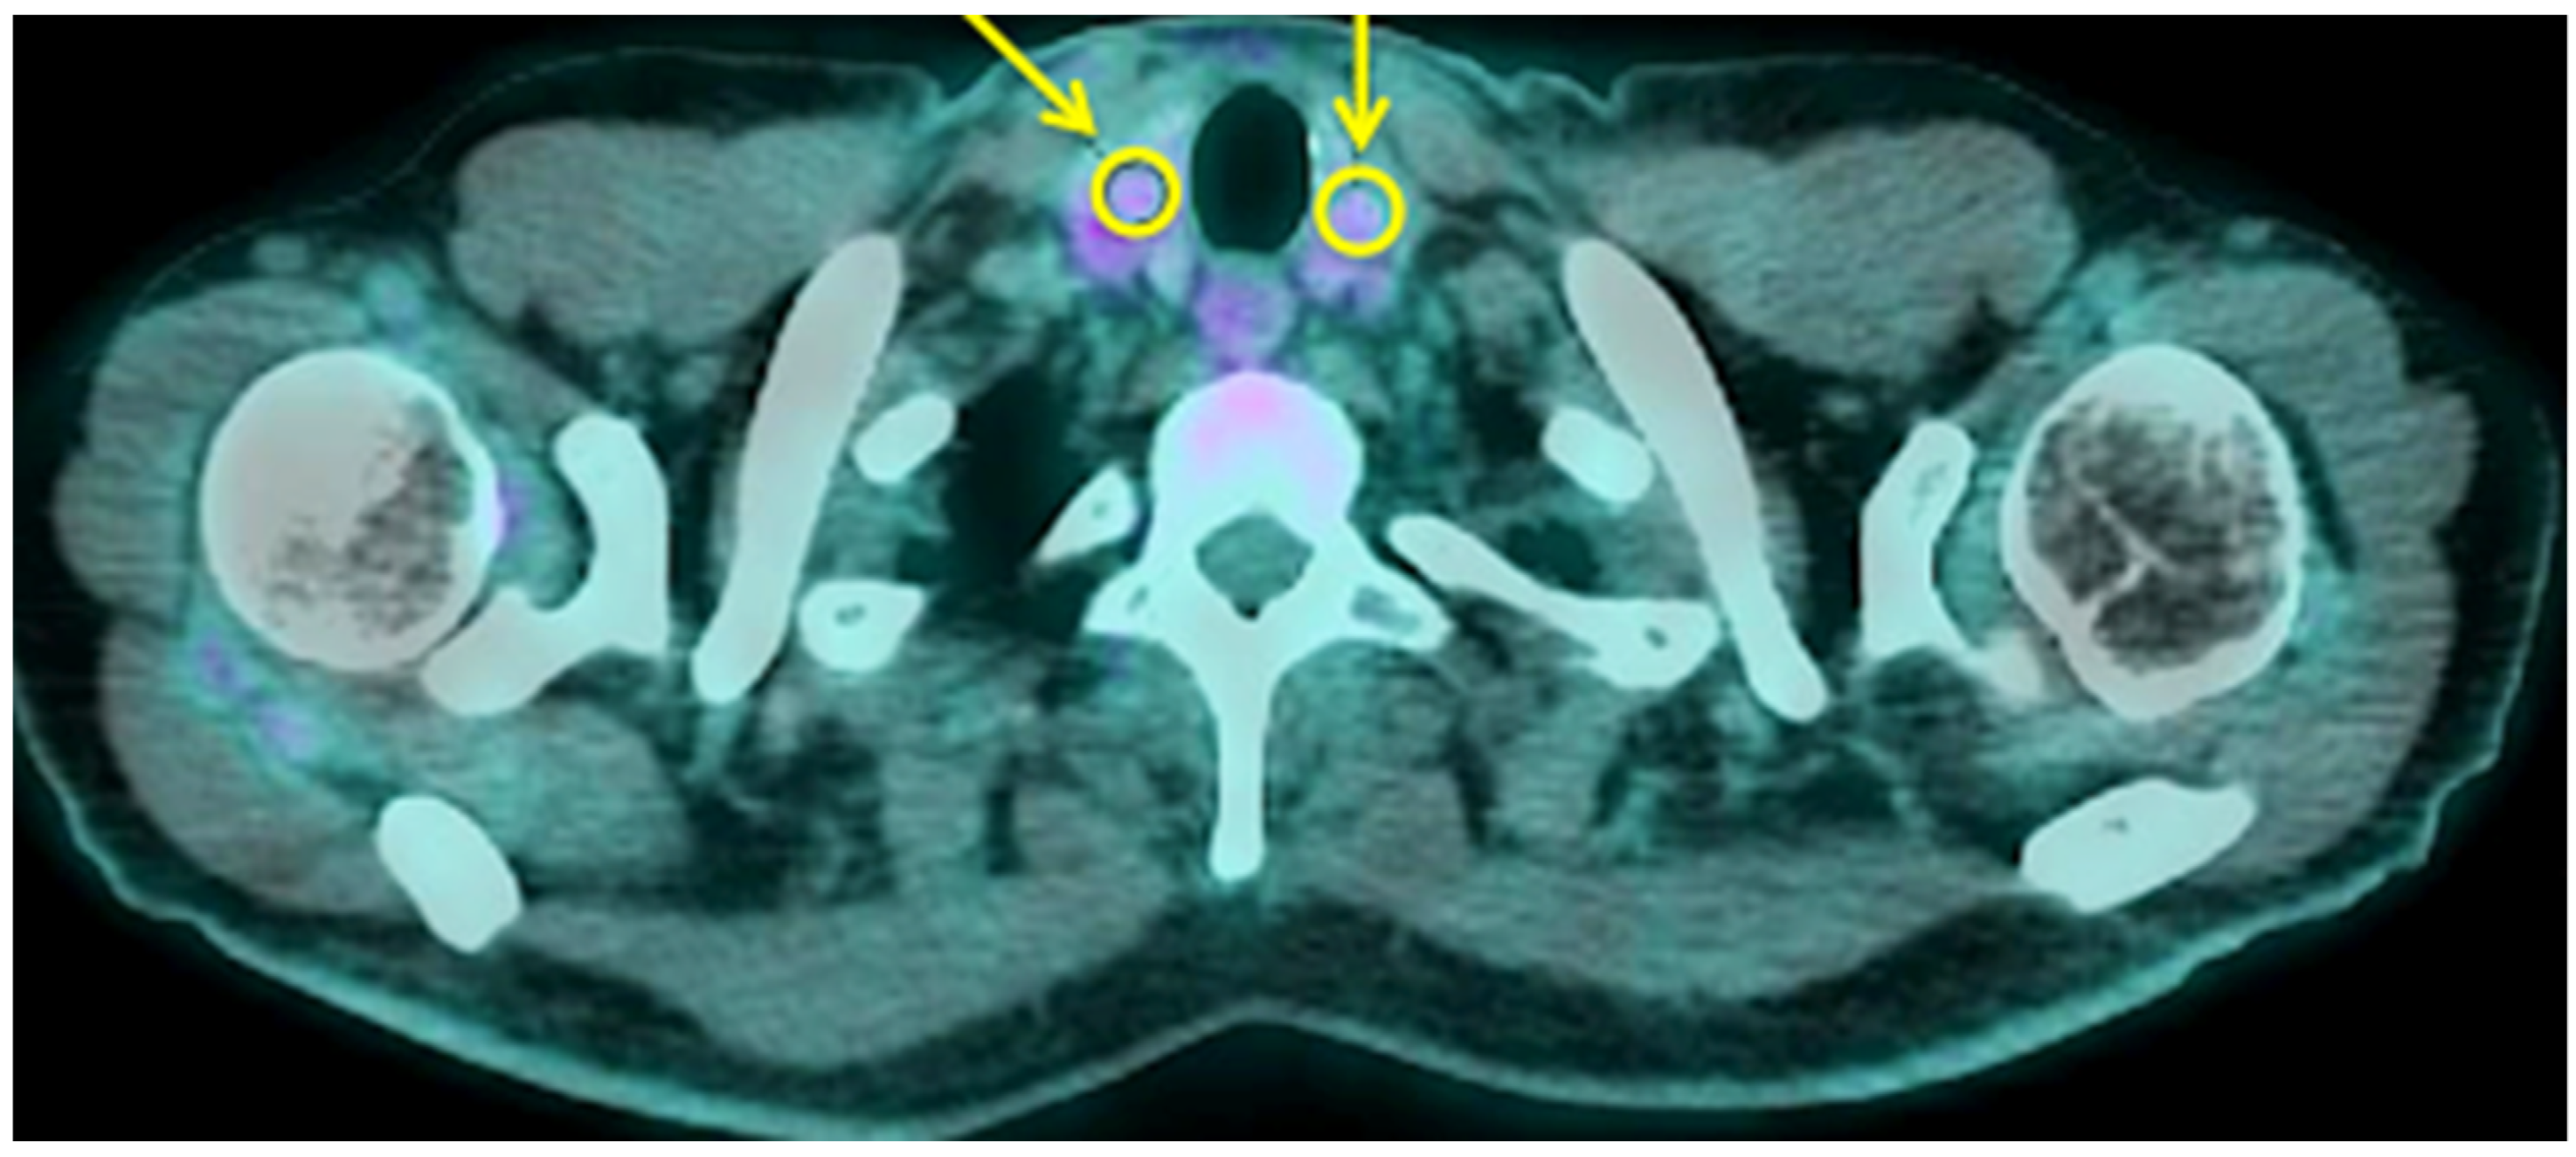

3.2. Thyroid and Adrenal Gland Analysis